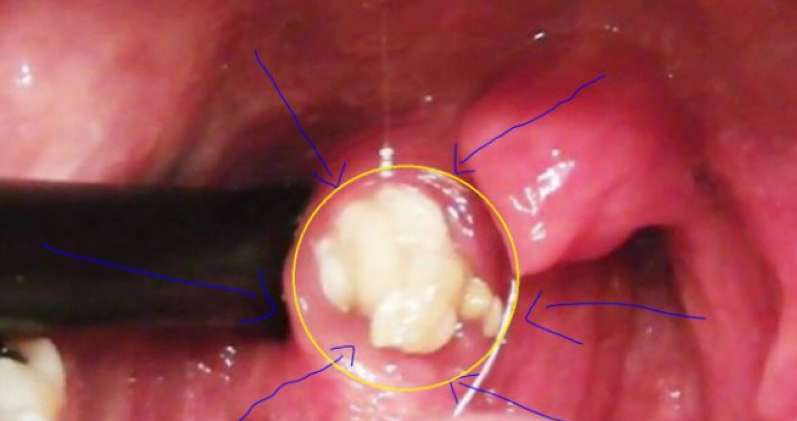

تنتج الرائحة الكريهة في الفم عن طريق مجموعة من الأشياء؛ إما عن عدم انتظام نظافة الفم، أو التدخين. الشيء الذي يجعل البكتيريا تتراكم على مستوى تجويف الفم، والتي قد تنتج عن التهابات، جفاف الفم، شرب الشاي والقهوة، تسوس الأسنان، غير أن الأمر قد يكون من خلال مشكل آخر قلما يعلمه الأشخاص المصابين بهذا المشكل على مستوى الفم، إنه الكازين على اللوزتين، وهو عبارة عن تراكم الأطعمة، المخاط والخلايا الميتة في الأغشية المخاطية في الحلق، إذ تتراكم في هذه الثقوب لتشكل بقعا بيضاء، مع المدة تعطي رائحة كريهة بالفم.

– فرشاة الأسنان: أمام مرآة قوم بمحاولة إزالة هذه الرواسب، عن طريق محاولة رفع اللوزتين، ثم حاول تحريك الفرشاة لإزالته، بعد ذلك قوم بغسل الفم جيدا.

– مسحة القطن-coton tige-: قوم بتبليله بالماء، ثم اضغط على المكان الذي تتواجد به هذه البقع البيضاء نحو الخارج، ثم اغسل فمك بواسطة حمام الفم الذي يباع في الصيدليات أو الطبيعي.